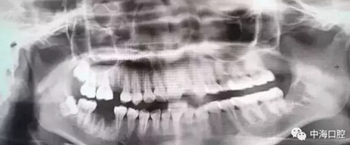

由于智齒的生長位置特殊,導(dǎo)致了拔除難易不同,如智齒出現(xiàn)橫著長或者靠近牙神經(jīng)的話,則難度會較高,一般人只需拍個口腔全景片,但相對于智齒靠近神經(jīng)管的情況,還可能需要拍CT,這都很考驗牙醫(yī)的技術(shù)。

拔牙非小事,請不要拿成本衡量牙醫(yī)的價值!

下面這兩張圖,據(jù)說拔牙費時1.5小時,收費14000元。